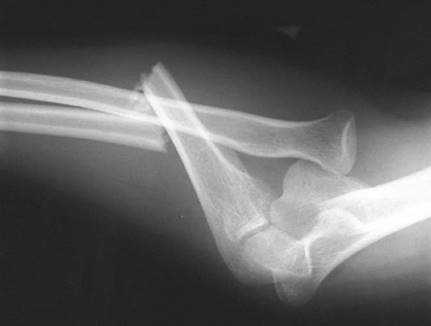

What does this radiograph tell you and what are your immediate concerns about the patient?

This lateral radiograph shows a dislocation of the left knee. This is usually a high-energy injury so I would be concerned about general patient status and other injuries. As far as this injury is concerned I would be most worried about a popliteal artery injury, which occurs in around 25 % of patients with this injury.

How do you carry out an initial assessment of this patient?

I would assess and document the neurovascular status of the limb before reducing this dislocation, under sedation, as an emergency. After reduction I would again perform a careful neurovascular examination. If there is any suggestion of vascular injury, exploration or angiography is indicated. A โnormalโ pulse may not exclude injury; an ankleโbrachial pressure index of less than 0.9 is abnormal.